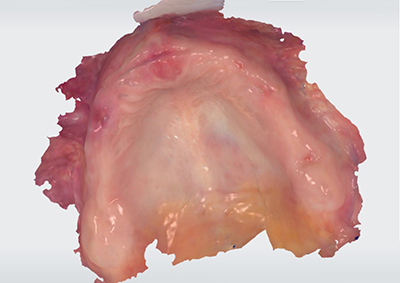

Utilisée en mode intra-oral, elle permet de numériser les crêtes édentées de patients ne disposant pas de références prothétiques existantes et/ou exploitables.

Fig. 03 : numérisation des crêtes édentées d’un patient.

Il convient toutefois de rappeler que l’empreinte optique ne permet pas l’enregistrement de la dépressibilité muqueuse ni du joint périphérique. Elle autorise donc uniquement la réalisation d’empreintes primaires chez ces patients. L’empreinte obtenue est de nature muco-statique et s’accompagne fréquemment de surextensions, rendant nécessaire, dans un second temps, la réalisation d’une empreinte anatomo-fonctionnelle selon une technique conventionnelle à l’aide d’un porte-empreinte individuel(12).

L’utilisation de la caméra en mode intra-oral peut également présenter un intérêt chez les patients dentés nécessitant la mise en bouche d’une prothèse amovible complète immédiate transitoire, notamment lorsque la mobilité dentaire ou certaines malpositions rendent difficile la prise d’empreinte conventionnelle(13).

La qualité de l’acquisition repose alors sur le respect de recommandations cliniques simples mais essentielles. Il est conseillé d’éteindre le scialytique, de mettre en place une canule d’aspiration afin de limiter la présence de salive, et de sécher soigneusement les muqueuses et les crêtes édentées à l’aide de compresses. Un travail à quatre mains, en particulier à la mandibule, facilite l’écartement de la langue et des joues ; l’utilisation d’un écarteur de bouche peut également être indiquée afin d’éviter l’enregistrement numérique de zones indésirables, telles que la face interne des joues ou la langue. Les crêtes édentées peuvent par ailleurs constituer des zones de réflexion lumineuse importantes. L’application ponctuelle d’une poudre intra-orale permet, dans certaines situations cliniques, de matifier leur surface et d’en faciliter la numérisation.